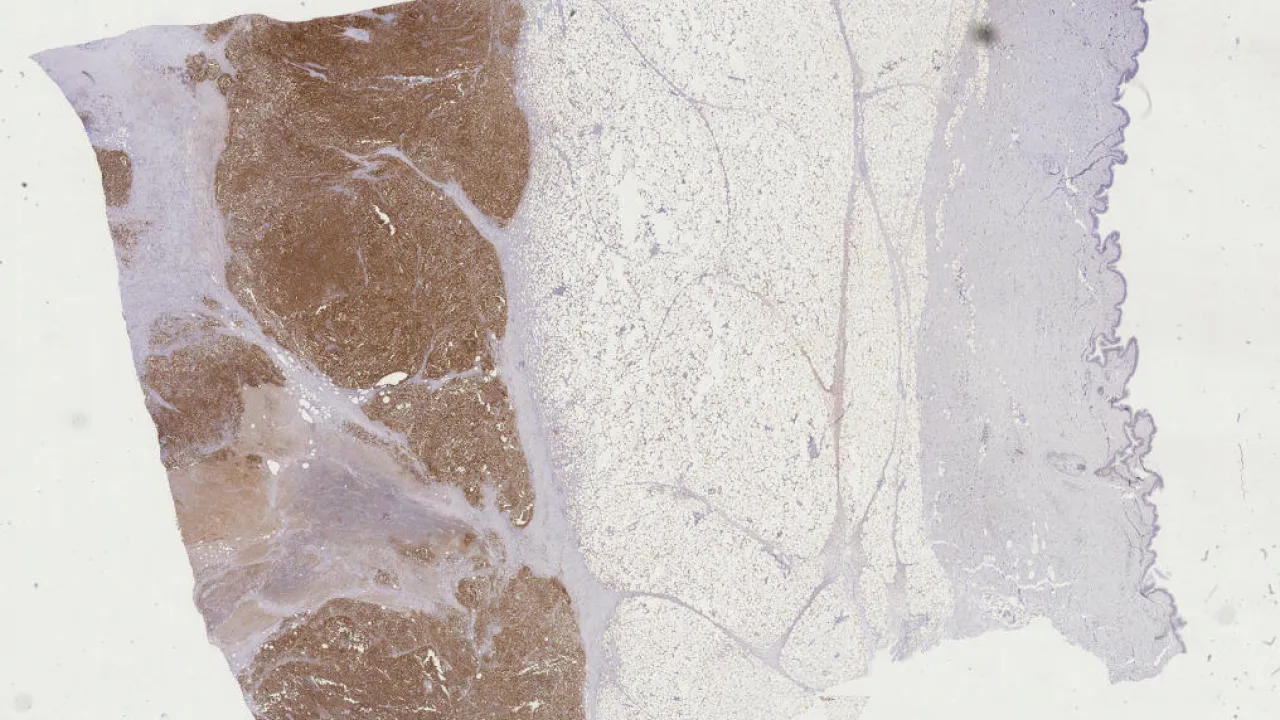

Breast, Epithelial-myoepithelial invasive carcinoma, S100 stain